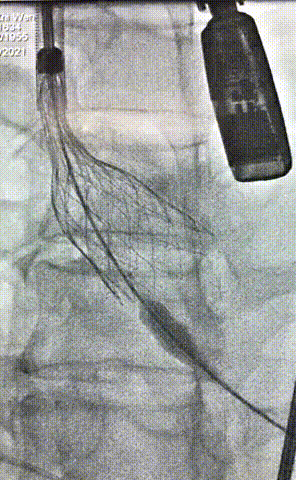

2.主动脉根部造影,瓣上钙化清晰,未见明显反流影;

4.180次/分快速起搏下以25mm TaurusAtlas球囊进行预扩张,扩张同时造影无明显腰征,无造影剂渗漏,双侧冠脉显影清晰;